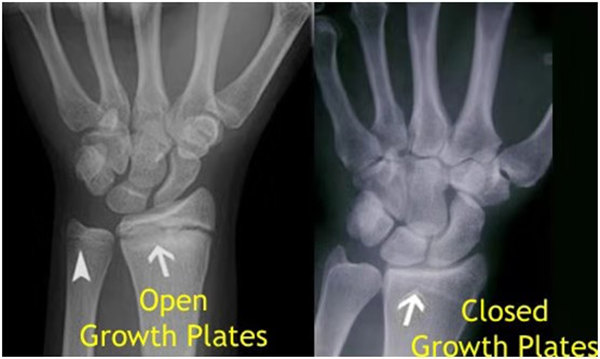

其實(shí)想要了解孩子的生長(zhǎng)發(fā)育情況或者說(shuō)孩子未來(lái)身高的趨勢(shì),測(cè)骨齡是個(gè)好辦法。臨床上通常拍攝兒童的左手正位X光片 , 采用《中華-05》骨齡標(biāo)準(zhǔn)對(duì)手腕骨發(fā)育程度進(jìn)行骨齡評(píng)價(jià)。

我們都知道,人體的高矮是由骨骼的生長(zhǎng)發(fā)育決定的,特別是下肢長(zhǎng)骨。長(zhǎng)骨呈長(zhǎng)管狀,在長(zhǎng)骨的兩端有一種專管骨骼生長(zhǎng)的骺軟骨,它與干骺端之間有一盤(pán)狀軟骨結(jié)構(gòu)稱為骺板(線),在幼兒的X光片上表現(xiàn)為一條較寬的透光帶。 (見(jiàn)下圖)

未成年時(shí)隨著年齡的增加骺軟骨端不斷骨化,骨骼就不斷增長(zhǎng)。當(dāng)骨骺線完全閉合時(shí)骨骼就停止生長(zhǎng),個(gè)子也就不再增長(zhǎng)了。一般骨骺端完全閉合的年齡是18~20歲左右。